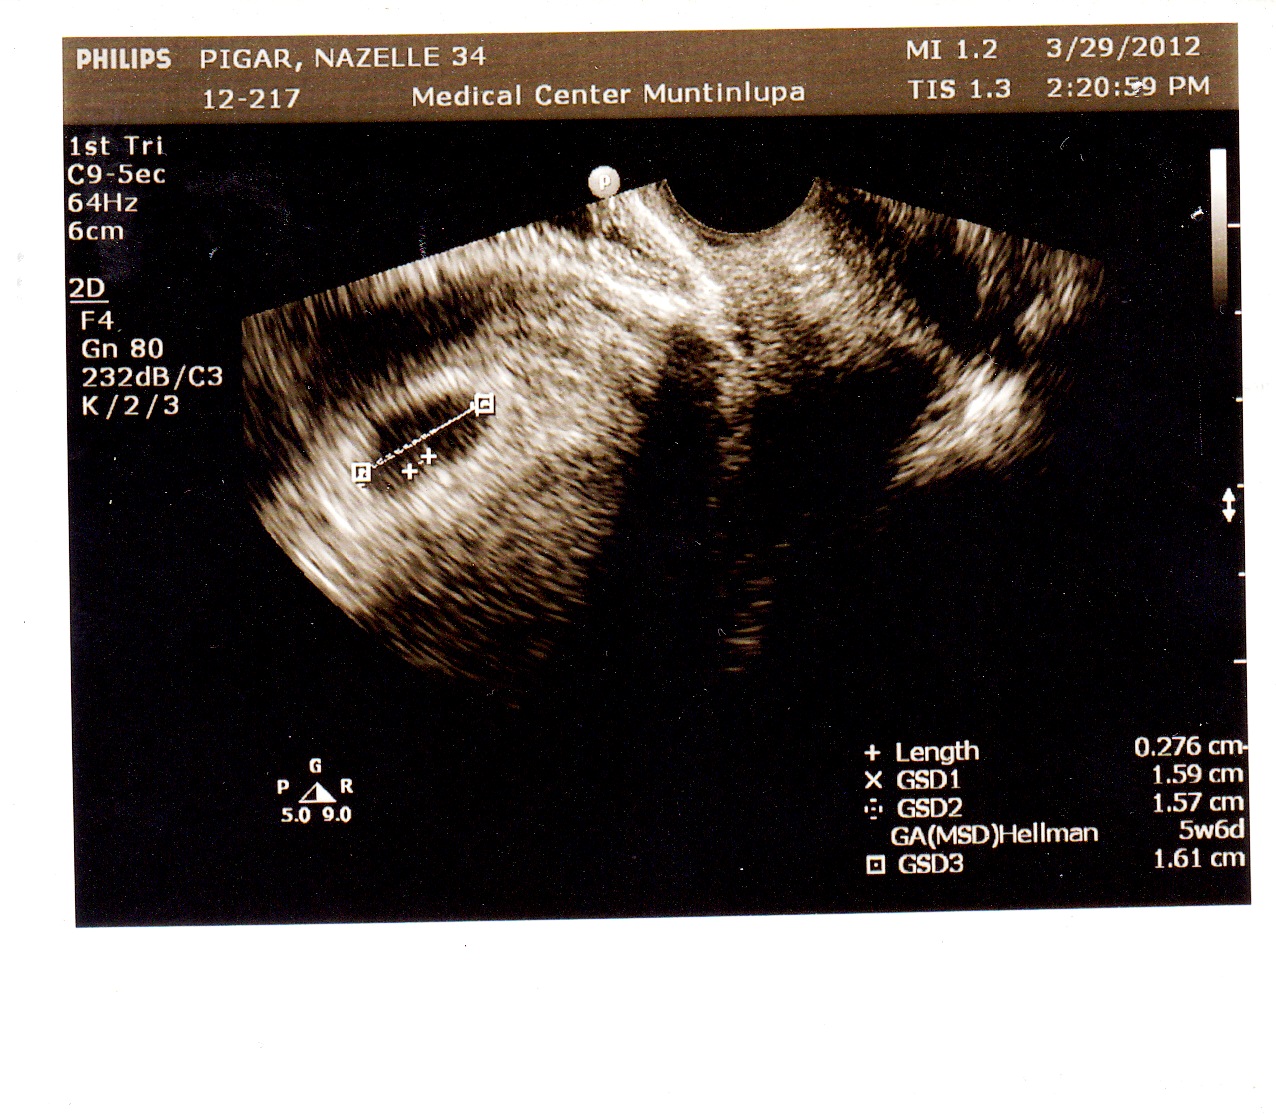

Expectant Mom Again D 5 Weeks 6 Days Trans Vaginal Us Result

Gestational Age Week 7 (Fetal Age:.

In general, if the MSD is ≥25 mm and no fetal pole or yolk sac can be identified on endovaginal scanning, then this suggests a failed pregnancy (anembryonic pregnancy). I'm afraid, possibly it's a null pregnancy. At us today, just showing yolk sac again, no fetal pole yet.

In my first ultrasound they only found a sac and a yolk sac, no fetal pole and said that I was measuring only 5 weeks (I thought I was about 6 1/2). We have the same EDD (3/17/10) At 6 weeks 2 days they saw a gestational sac and yolk sac but no fetal pole or heartbeat. It is approximately 2 mm in length at 5 weeks.